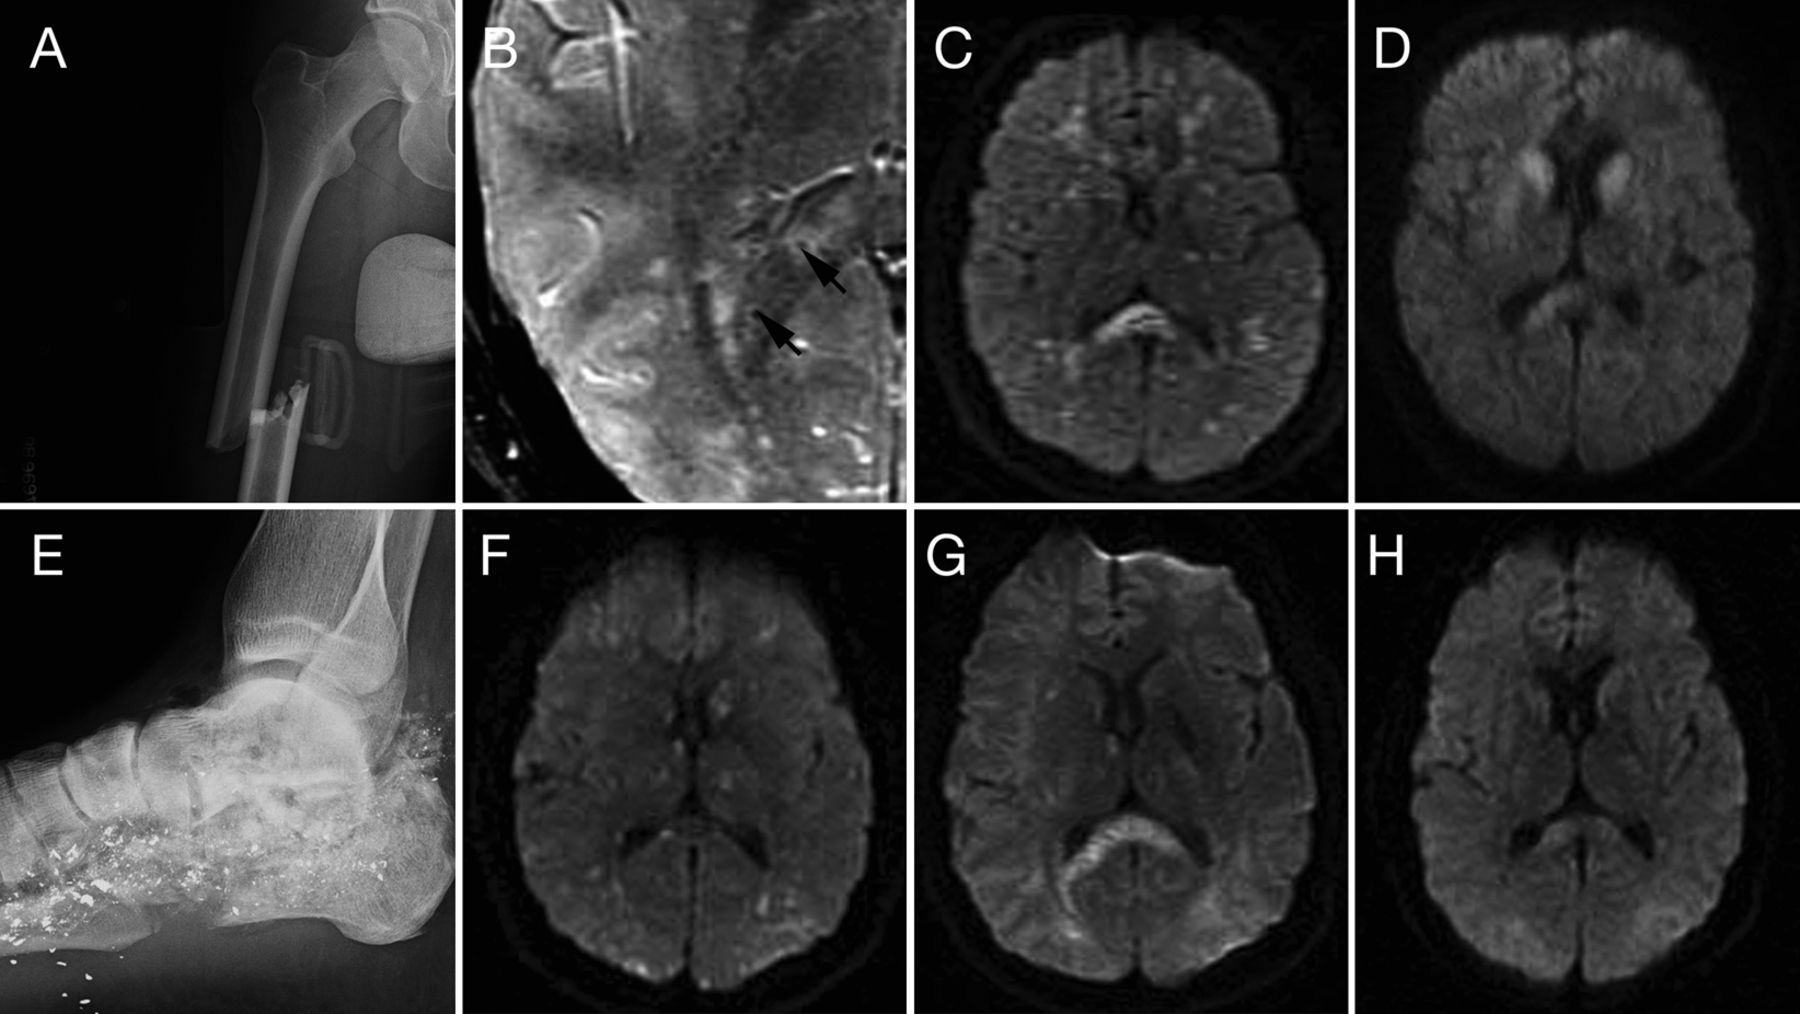

上一行(案例1):右腿的x光照片显示关闭midshaft股骨骨折(一个);第五天,轴向susceptibility-weighted成像序列显示多个点状的疫源地hypointense信号在整个大脑(黑色箭头标志)(B);多焦点的限制扩散模式(星际)diffusion-weighted成像序列(驾车)(C)和23天随访MRI显示分辨率的一些病变驾车序列(D)。较低的行(例2):x光照片的左脚和跟骨显示无数微小的金属碎片在软组织和骨骼和多个跟骨骨折与软组织肿胀(E);第一天首先MRI显示多个领域的限制扩散在酒后驾驶星际序列特征模式(F);7天随访MRI显示的微小病变进展汇合的模式(G);在30天随访MRI显示明显细胞毒性水肿(H)的决议。

一个42岁的男人被击中的左脚在他12岁的儿子在一次狩猎旅行。x射线显示多个左跟骨骨折与软组织肿胀(图E)。四个小时后,他的血压是暂时性的下降到83/55毫米汞柱。他的动脉血液气体显示pH值7.39,Po2158毫米汞柱,P有限公司237毫米汞柱,F我O281年arteriolar-alveolar梯度增加40%。他呻吟,自发地打开他的眼睛,而不是跟踪。有增加肌肉张力、反射亢进和双边巴宾斯基的迹象。他逐渐变得不那么敏感,5小时后伸肌姿态。他对气管插管的保护。胸部x光片是正常的。脑部MRI表现30小时后显示分散焦点星际减少扩散的模式(图F)。TTE显示肺内的分流。他成为tachycardic(脉冲到148次/分钟)和发热(39°C),并表现出大汗。他与加巴喷丁治疗、hydromorphone和美托洛尔。第二天他自发眼开。第一周后随访MRI显示附近解决之前diffusion-weighted成像(驾车)病变(图G在4周)与持续改进(图中,H)。他被转移到一个养老院。病人慢慢改善,6个月后,他和家人住在家里。残余赤字问题包括演讲、内存(短期和长期)、易怒、左上肢痉挛状态,左尺骨压缩神经病变、周围神经病变、止痛的步态。